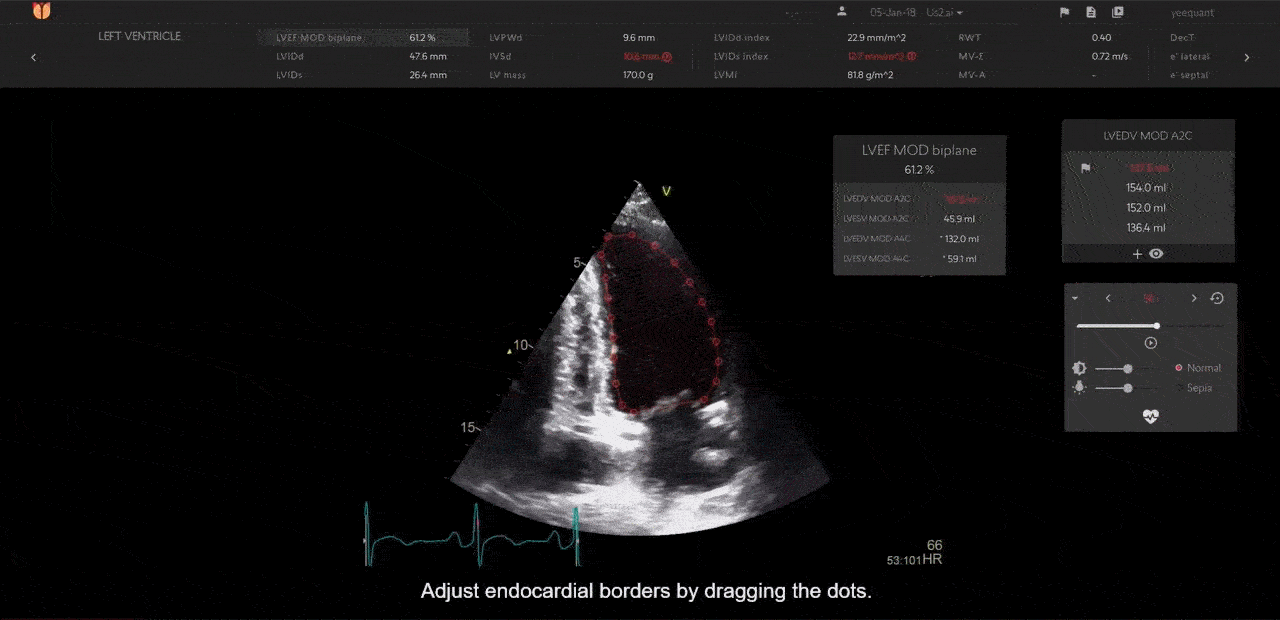

Mit dem echo COPILOT™ können Echtzeitberichte von jedem Ultraschallgerät erstellt werden. Von GE Vivid CARTs bis hin zu EchoNous Kosmos Mobilgeräten bietet us2.ai Lösungen für jedes Echo-Gerät und jeden Arbeitsablauf.

Echtzeit-Interpretation in 2D und Doppler